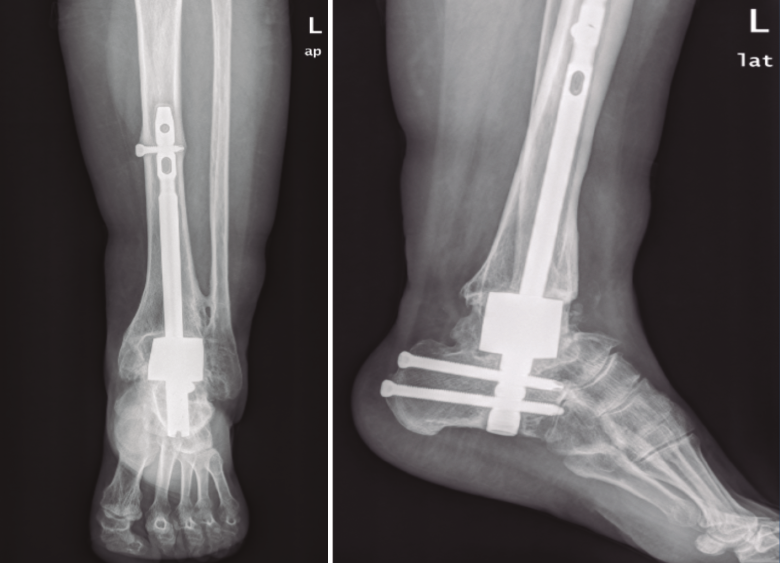

La utilización de espaciadores de tantalio en el tobillo asociados a un clavo tibiotalocalcáneo permite la artrodesis sin perder longitud del espacio articular, evitando la dismetría de miembros.

Hemos estudiado 4 casos de artrodesis tibiotalocalcánea con espaciador de calcáneo por fracaso aséptico de prótesis de tobillo. El tiempo de seguimiento medio ha sido de 26 meses en 3 de los casos recogidos (20-37 meses), aunque el tiempo de seguimiento en el caso intervenido más recientemente es de 7 meses. Los resultados fueron valorados utilizando las escalas de valoración visual analógica (EVA) y de la American Orthopaedic Foot and Ankle Society (AOFAS).

Todos los casos han presentado buenos resultados clínicos e integración radiológica del implante. No se han producido complicaciones relacionadas con el material y los pacientes han mostrado satisfacción con el procedimiento. Creemos que los espaciadores de tantalio son una opción útil y segura en la artrodesis por fracaso aséptico de prótesis de tobillo.

The use of tantalum spacers in the ankle associated with a transcalcaneal nail, allows arthrodesis without losing the joint space length, avoiding limb length discrepancy.

We have studied 4 cases of tibiotalocalcaneal arthrodesis with a tantalum spacer due to aseptic failure of the ankle prosthesis. The mean follow-up time was 26 months (20-37) in the first 3 cases and 7 months over the last. Results were evaluated using Visual Analogue (VAS) and American Orthopaedic Foot and Ankle Society (AOFAS) scales.

All cases have presented good clinical results and radiological integration of the implant. There have been no complications related to the material, and patients have shown satisfaction with the procedure. We believe that tantalum spacers are a useful and safe option in arthrodesis due to aseptic failure of ankle prostheses.